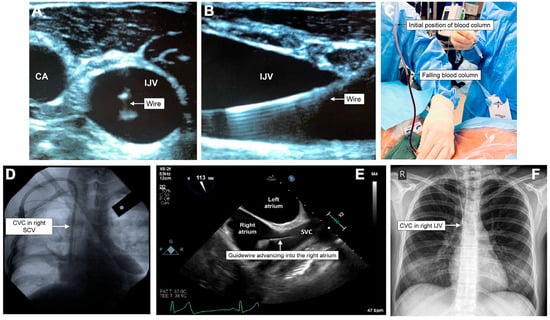

| Arterial Puncture | Combination blood color and pulsatility assessment, pressure manometry, and dynamic USS for needle tip position. | Often, no invasive management is required apart from external compression if it is identified before further cannulation. |

| Arterial Cannulation | Combination of blood color and pulsatility assessment, pressure manometry + waveform analysis, and dynamic USS for catheter position. | Leave the catheter in situ, and follow the pathway documented in Figure 5. |